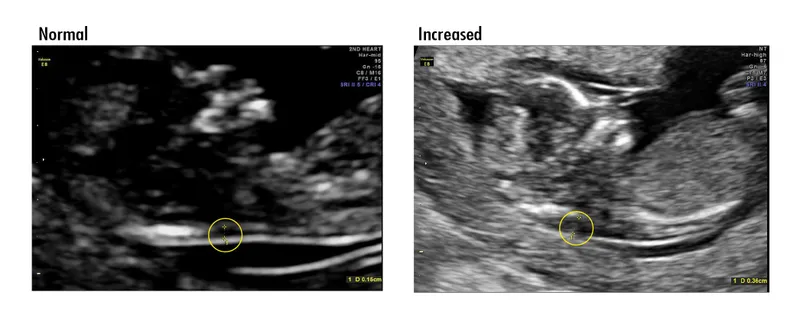

Amniocentesis - The Fluid Truth

Procedure: Transabdominal needle aspiration of amniotic fluid using ultrasound guidance, collecting fetal cells (amniocytes) for analysis.

Timing: Performed between 15-20 weeks gestation. Can be done later for fetal lung maturity assessment.